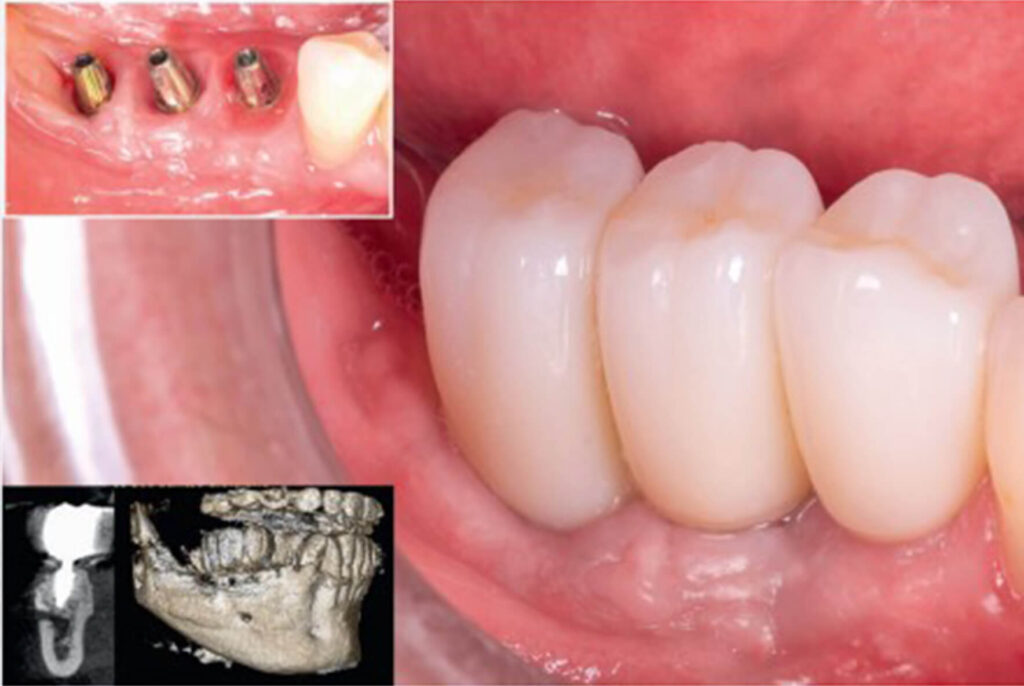

Reconstrução óssea tridimensional em regiãoposterior mandibular conforme a técnica de Khoury: 2 anos de acompanhamento

DOI: https://doi.org/10.71440/2675-5610.10.4.25.530-533.art Recebido: junho/2025 Revisado e aceito: julho/2025 Como citar:Barros LL, Urteaga VM, Salazar GB, Alberto W, Sá BCM, Skiba THI. Reconstrução óssea tridimensional em região posterior mandibular conforme a técnica de Khoury:2 anos de acompanhamento. ImplantNews 2025 Jul-Ago;10(4):530-3 1. Departamento de Implantodontia e Reabilitação Oral da SOEP – Porto Velho – RO Endereço correspondência:Lucas […]